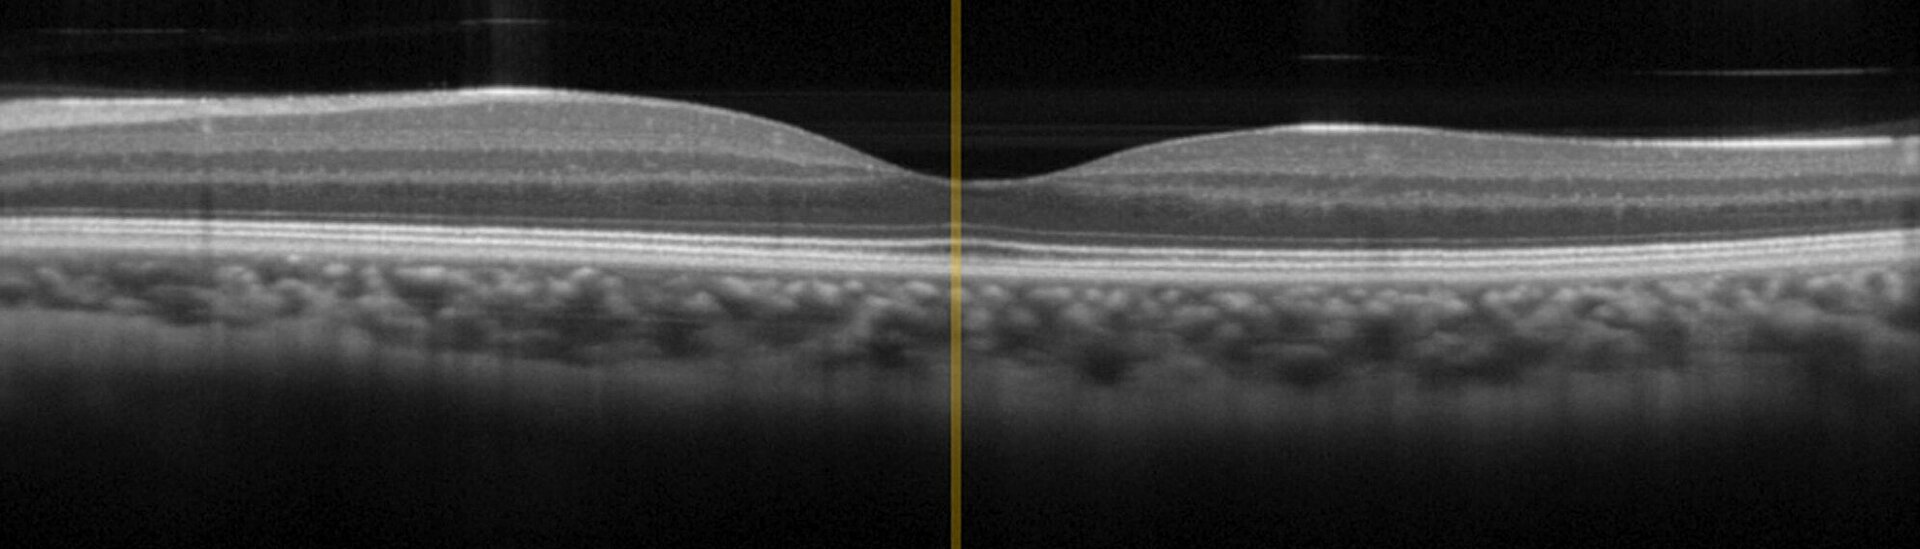

OCT是一种基于0.8微米至1.4微米波长范围内的宽带红外光的干涉成像技术,可实现优化的组织穿透性。OCT在眼科领域已经达到“黄金标准”,而且最近在皮肤科领域的应用也日益广泛,例如用于诊断皮肤癌。与传统的创伤性诊断手段相比,OCT可以更快速地提供结果并减轻对患者造成的副作用和压力。